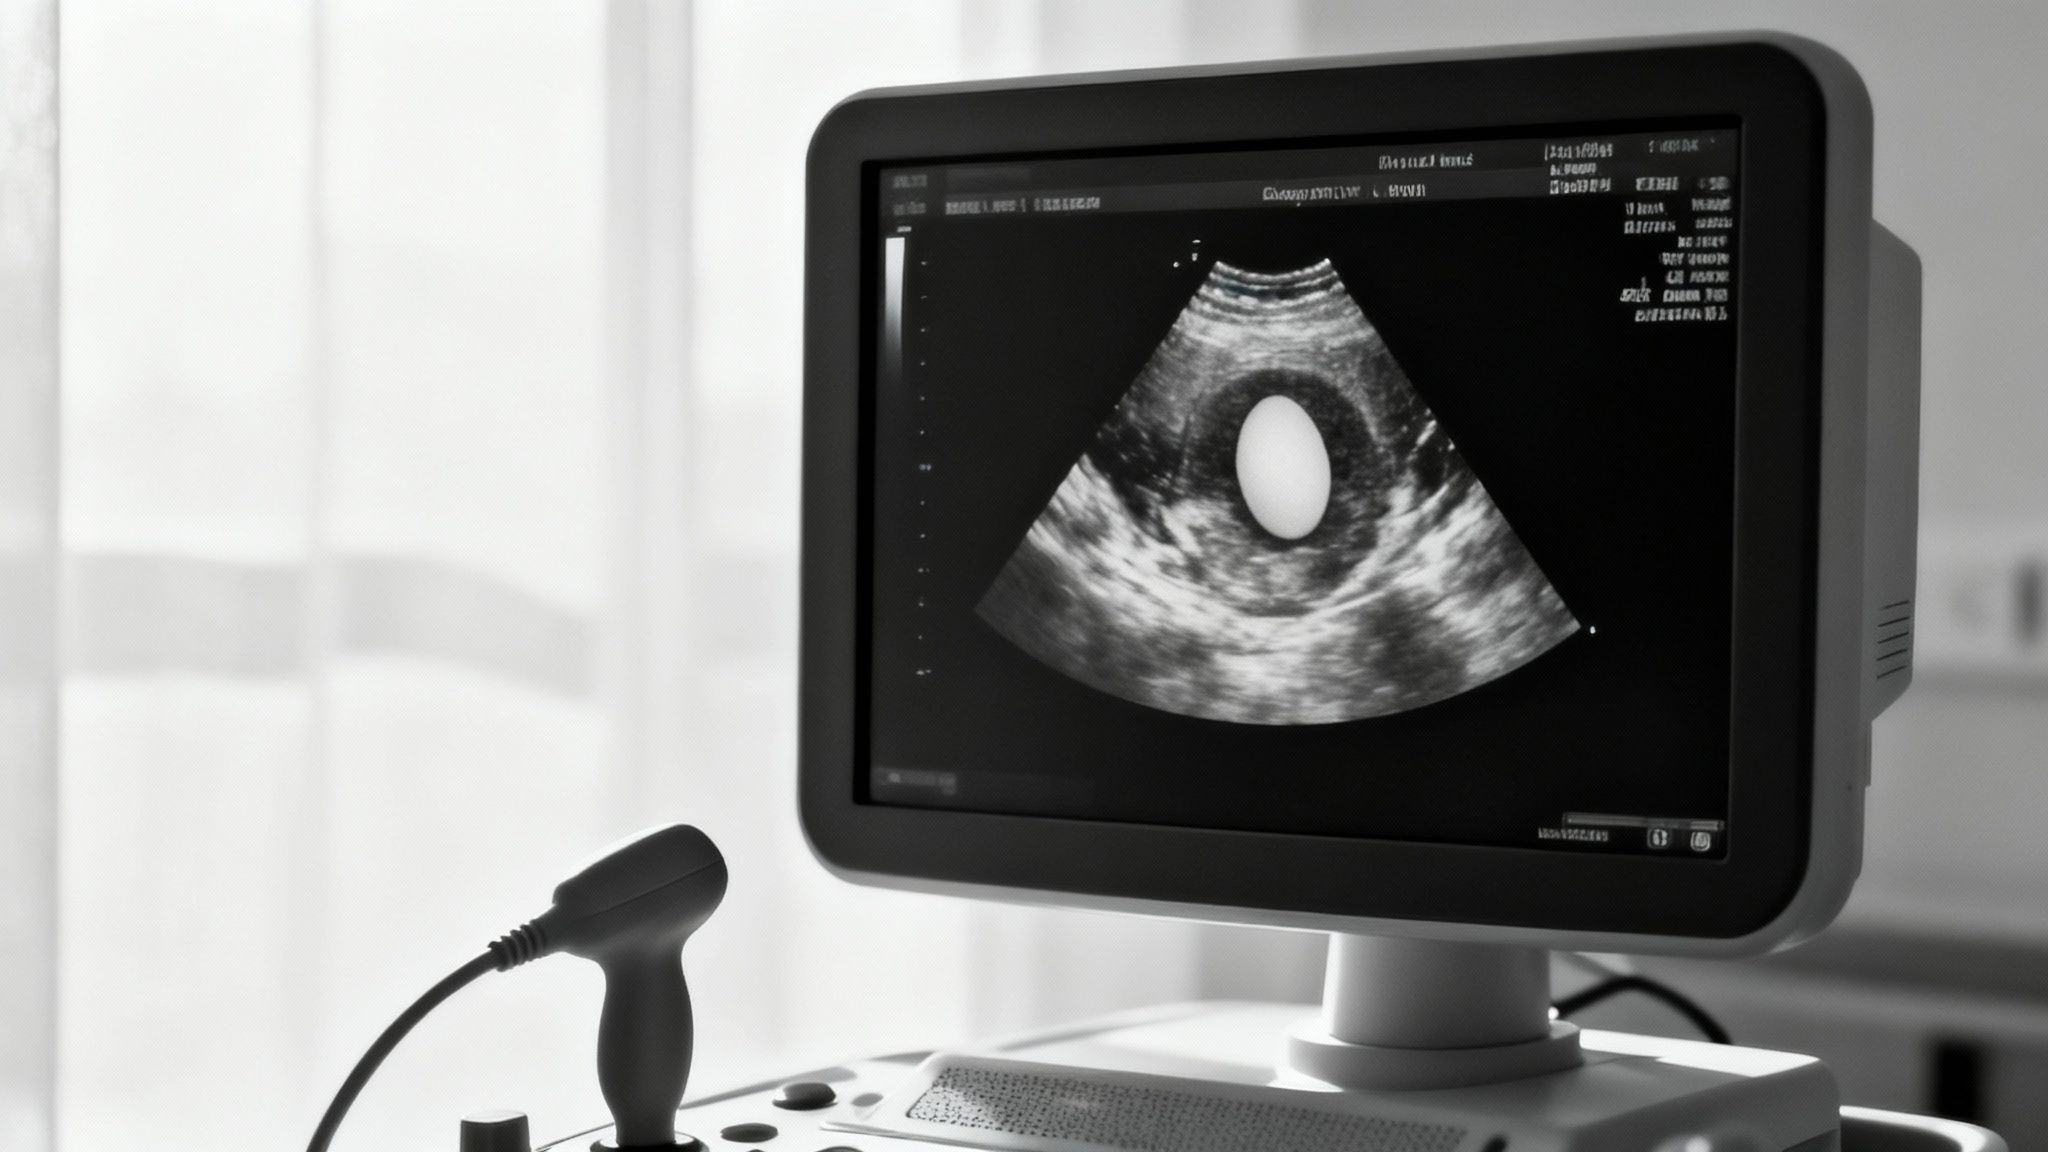

Le diagnostic est la toute première étape. Pour confirmer ou écarter une suspicion de fausse couche, les médecins s'appuient principalement sur deux examens. Une échographie est généralement réalisée pour observer l'utérus, vérifier la présence d'un embryon et contrôler si son cœur bat. C'est un moment souvent chargé en émotions.

Parallèlement, une prise de sang peut être demandée pour mesurer le taux de l'hormone de grossesse, la fameuse hCG. Si ce taux ne progresse pas comme attendu – il est censé doubler toutes les 48 à 72 heures en début de grossesse – ou s'il diminue, cela peut malheureusement indiquer que la grossesse s'est arrêtée.